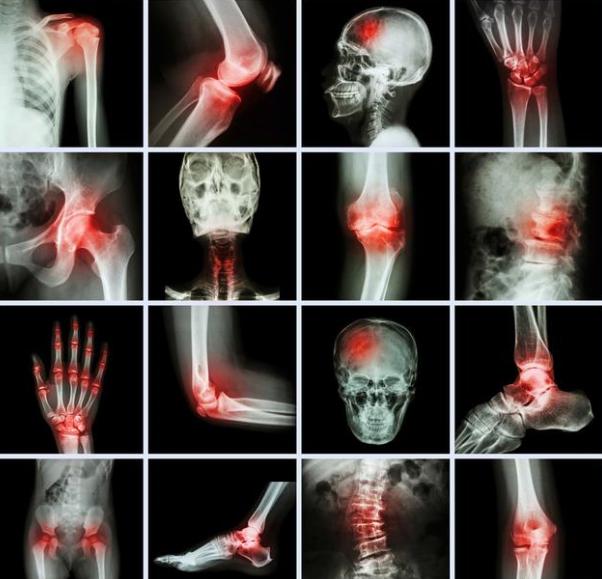

10、对于急性椎体骨折、多个椎体骨折、髋关节骨折、桡骨远端骨折后引起慢性疼痛的患者,使用躯干矫形器(如背带、胸衣、姿势训练、支持装置等)可以通过减少骨折部位的负荷和调整骨折部位来减轻疼痛。然而,长期的支撑可能导致肌肉无力和进一步的失去调节。

12、有近期疼痛性椎体骨折、髋关节骨折、桡骨远端骨折且保守治疗失败的患者,当由经验丰富的医生进行手术时,可作为干预措施(如后凸成形术、椎体成形术、髋关节置换术等)。